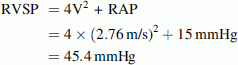

Initial ED bedside echocardiography was performed (see Video Clips S1, S2, S3, S4, and S5, available as supporting information in the online version of this paper). Examination of the heart with a low frequency array cardiac probe in the apical four-chamber view revealed right ventricular hypertrophy and a combined atrial septal defect (ASD) and ventricular septal defect (VSD) with no pericardial effusion (Fig. 1; Video Clip S1). A color Doppler subcostal view revealed a left-to-right shunt from the left ventricle to the right atrium (Fig. 2; Video Clip S2). Right ventricular outflow tract view (RVOT) evaluation of the aortic valve revealed a bicuspid aortic valve (Fig. 3; Video Clip S3). Parasternal short axis view at the level of the papillary muscles showed right ventricular pressure and volume overload with a D-shaped left ventricle present during both systole and diastole and a large dilated right ventricle (Fig. 4; Video Clip S4). Color Doppler evaluation of the tricuspid valve in the right ventricular inflow tract view (RVIT) revealed tricuspid regurgitation (Fig. 5; Video Clip S5). In addition, in the RVIT view (Fig. 6), continuous wave Doppler revealed tricuspid regurgitation with a 2.76 m/s regurgitant jet. Right ventricular systolic pressure (RVSP) was estimated elevated at 45.4 mmHg (greater than 25 mmHg is abnormal) from this tricuspid regurgitant jet velocity using the modified Bernoulli equation and combining this with an estimate of the right atrial pressure (RAP) [1]. Right ventricle systolic pressure (RVSP) = pressure gradient between the RV and RA = 4 × [tricuspid regurgitant Doppler jet velocity (meters/second)]2 + right atrial pressure (RAP) [1]. Right atrial pressure was estimated at 15 mmHg, as the patient had an inferior vena cava (IVC) diameter >2.1 cm and had less than 50% inspiratory collapse of the IVC in the subcostal view of the IVC going into the right atrium (Fig. 7) [1]. Using the modified Bernoulli equation and RAP estimation using IVC inspiratory collapse method recommended by the American Society of Echocardiography [1]:

RVSP = [ΔP (between the RA and RV) + RAP] (valid with no pulmonic stenosis)

∆P may be calculated from the tricuspid regurgitant (TR) jet velocity using the modified Bernoulli equation:

In our patient: